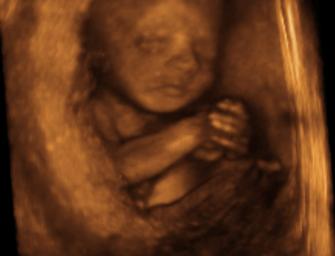

Picture of an abortion around 26 weeks